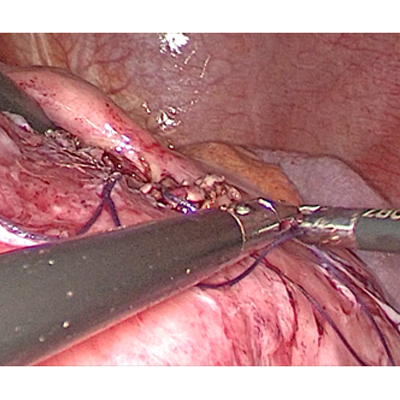

LAPAROSCOPIC SURGERY FOR RECTAL CANCER

ADVANCE LAPAROSCOPIC SURGERY